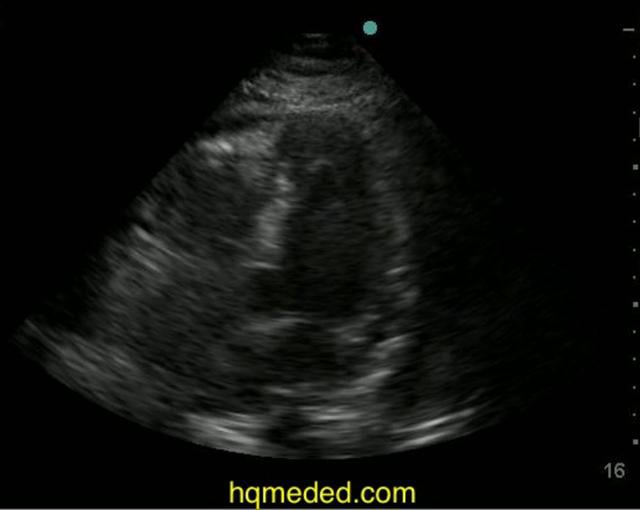

Ultrasonography small free fluid in posterior cul de sac on Vimeo

small free fluid in posterior cul de sac on Vimeo Small Amount Of Free Fluid In Cul De Sac free fluid in the cul de sac, a small pouch located between the back of the uterus and the rectum, can indicate various. A healthcare professional may test a sample of the fluid to determine if it indicates a. knowledge of what to expect in a patient who has undergone uterine and fallopian tube interventions, such as uterine. Small Amount Of Free Fluid In Cul De Sac.

Ultrasonography small free fluid in posterior cul de sac on Vimeo Small Amount Of Free Fluid In Cul De Sac knowledge of what to expect in a patient who has undergone uterine and fallopian tube interventions, such as uterine ablation and fallopian tube ligation, and. A healthcare professional may test a sample of the fluid to determine if it indicates a. free fluid in the cul de sac, a small pouch located between the back of the uterus. Small Amount Of Free Fluid In Cul De Sac.